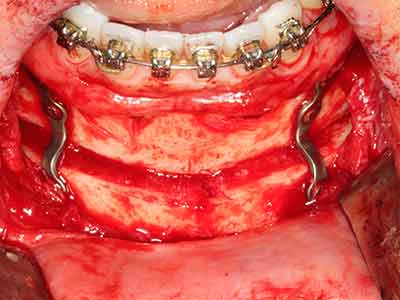

Wie sich in der Vergangenheit gezeigt hat stellt prinzipiell jeder knochenchirurgische Eingriff eine mögliche Indikation für die Piezochirurgie dar. So lässt sich die Präparation des mobilen Segmentes bei der Distraktionsosteogenese (Abb. 23-25) und der Sandwichosteotomie mit speziellen Ansätzen bewerkstelligen, ohne die für den Erfolg beider Techniken essenzielle Blutversorgung des krestalen Anteils zu gefährden (Gonzalez-Garcia, Diniz-Freitas et al. 2008).

Rein kieferchirurgische Indikationen ergeben sich unter anderem in der orthognathen Chirurgie, bei der Genioplastik (Abb. 27-30) sowie der Orbitadekompression bei Patienten mit fortgeschrittener endokriner Orbitopathie bei Morbus Basedow (Ponto, Zwiener et al. 2014). Zudem finden Piezogeräte je nach Klinik Anwendung in der kraniofazialen Chirurgie sowie bei der Entfernung von Schädelbasistumoren.